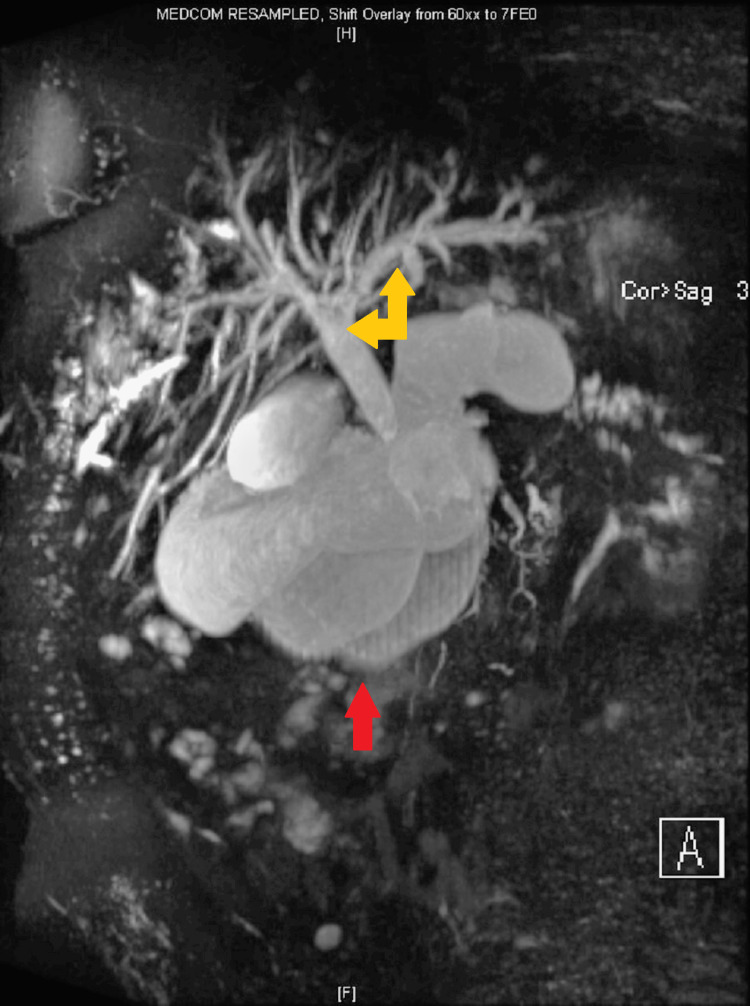

CT abdomen suggested recurrence of the pseudocyst in the pancreatic head, causing compression of the CBD and PD leading to dilatation of upstream PD, CBD, and intrahepatic biliary ducts. There was a further large cyst measuring 6.6 x 3.7 cm posterosuperior to the pancreas along with a larger right renal cyst. MRI confirmed evidence of chronic pancreatitis and two pancreatic pseudocysts. One of the cysts in the head of the pancreas measuring 4.8 x 4.6 cm was causing local pressure effect on the CBD, and there was intra and extrahepatic biliary dilatation with the CBD measuring up to 15 mm (previously 13 mm) (Figure 3). The cyst was also causing compression of the pancreatic duct, which was dilated to approximately 7 mm. The other large peripancreatic cyst measuring about 7 x 4 cm located posterosuperior to the body of pancreas had ruptured causing collection sized 12.9 x 11.2 x 13.0 cm, compressing on the right renal capsule (Figure 4).